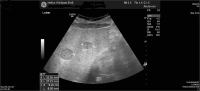

Abbildung 3: Leber mit hypodensen Läsionen, die größte im Segment VI bis 3,7 cm im Durchmesser.

Keywords: hypodense LäsionLeberOnkologieSonographie